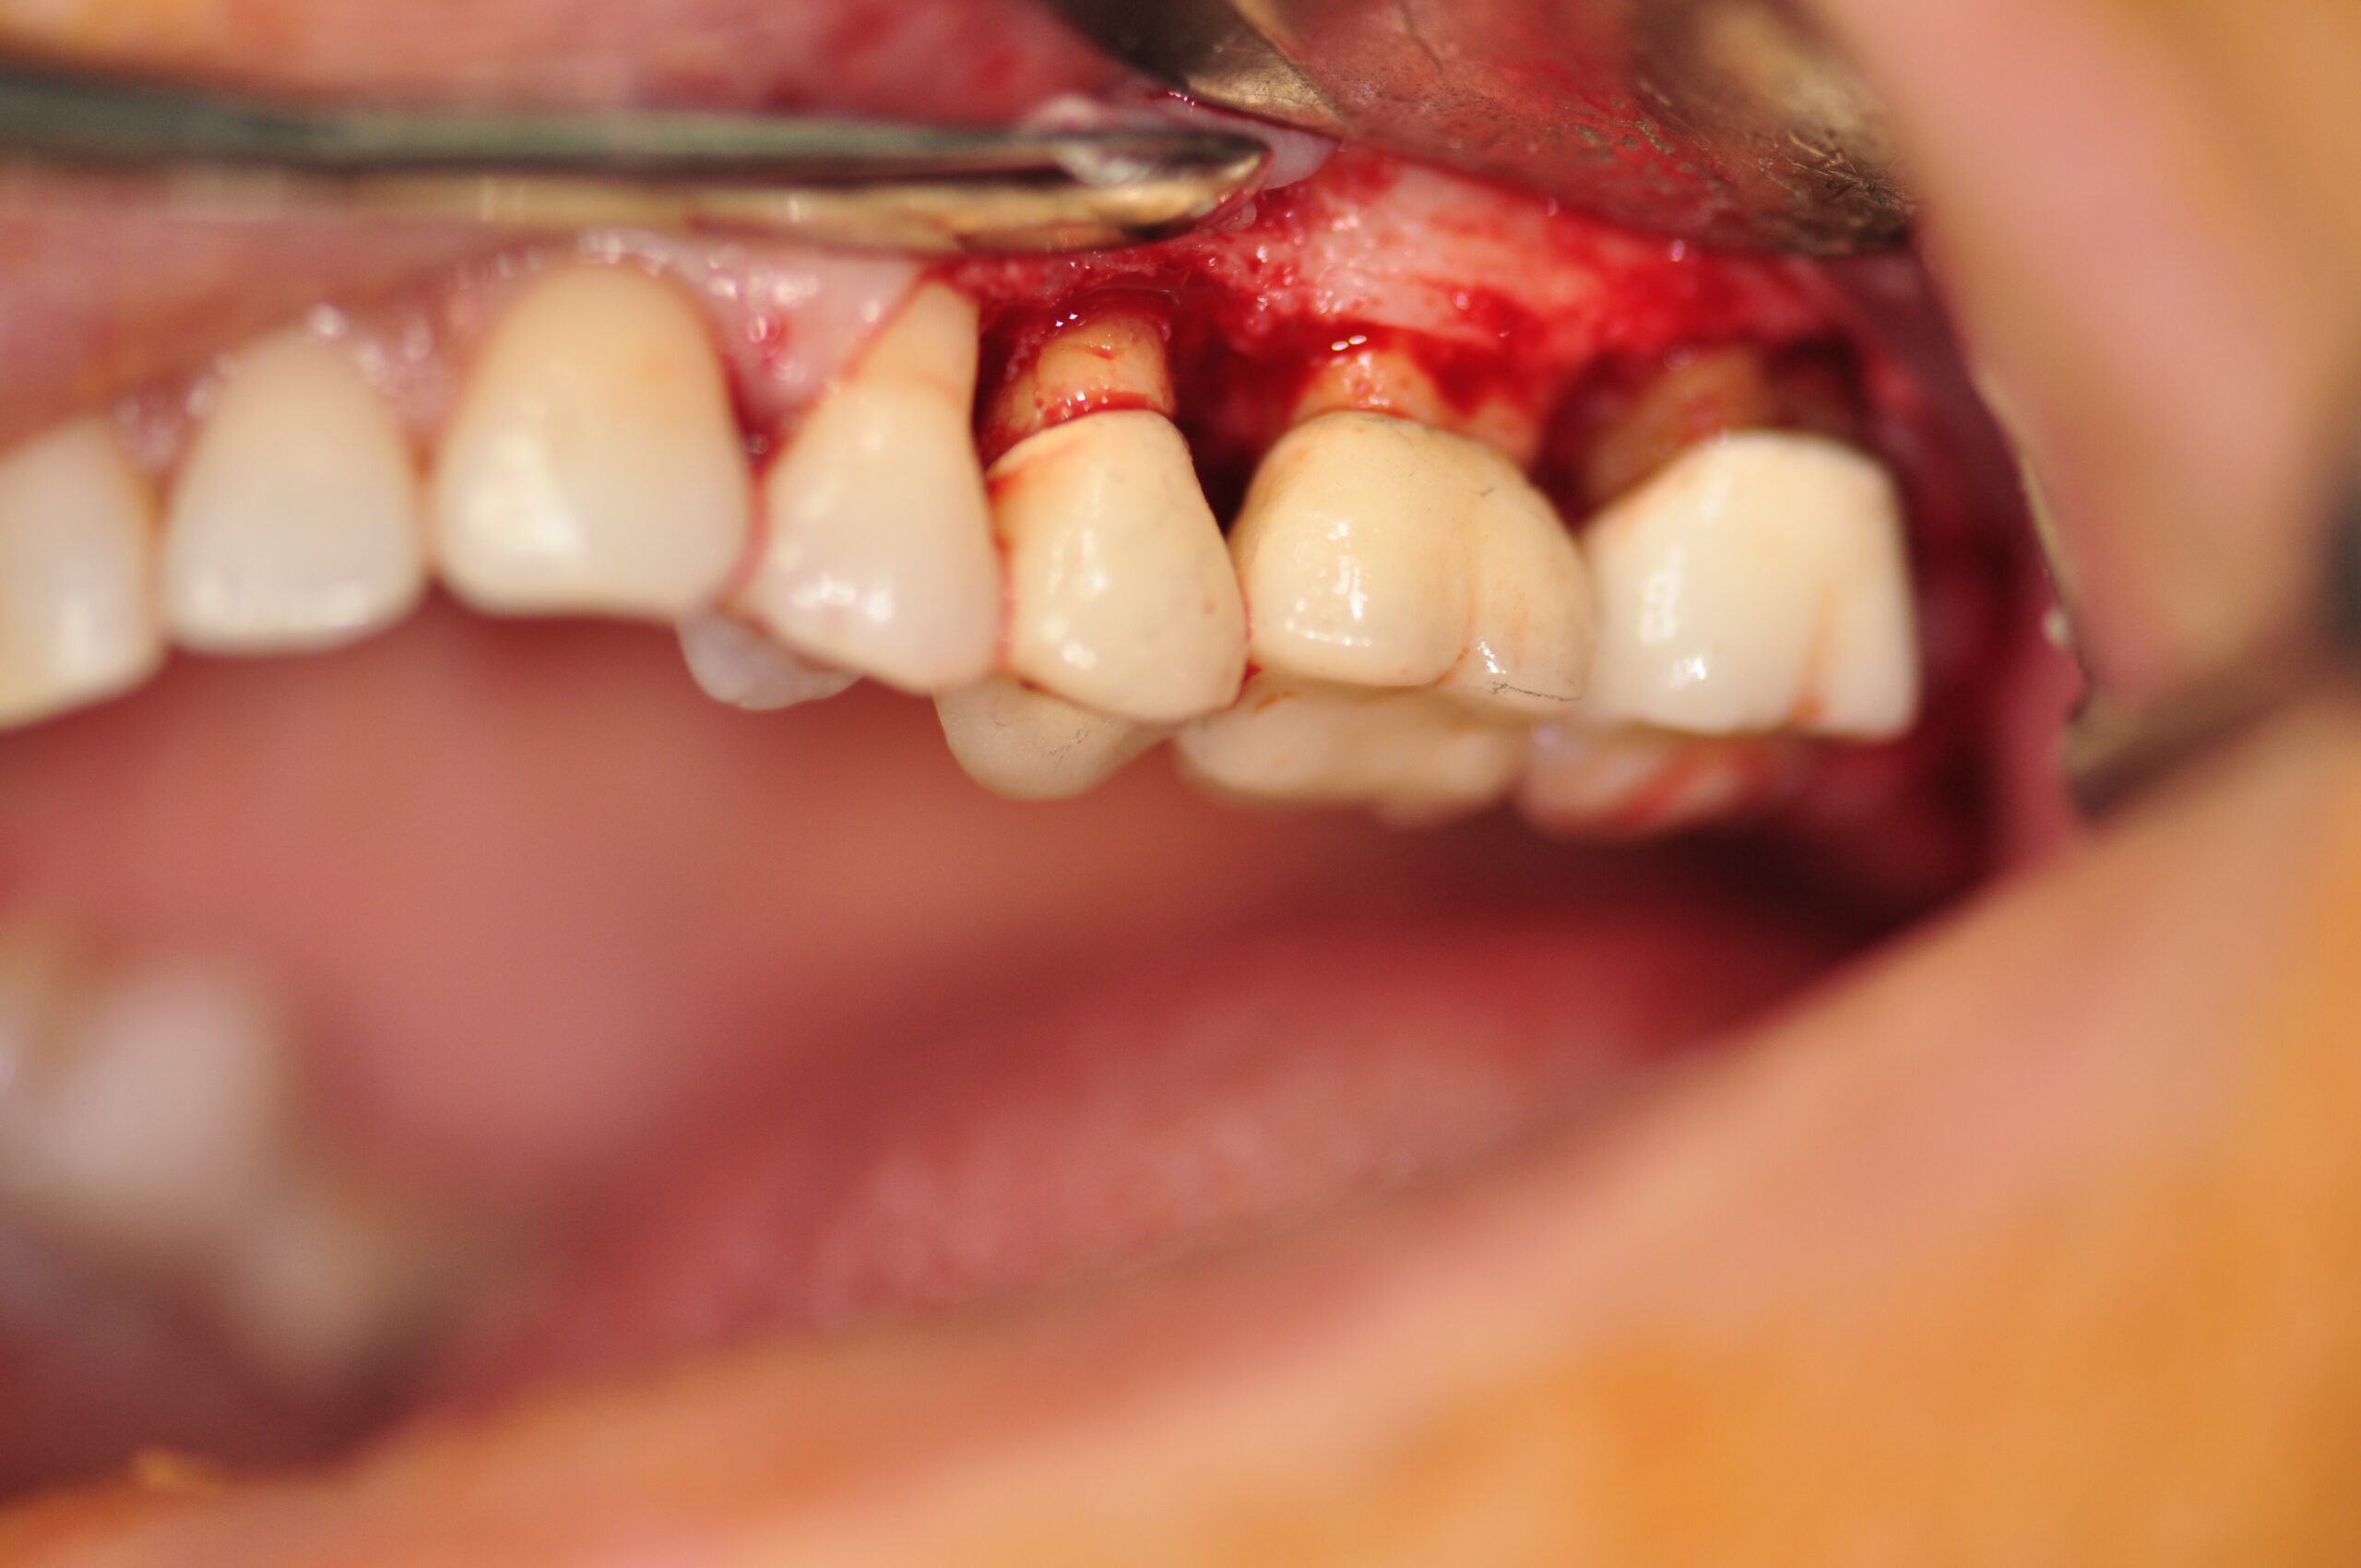

Celles-ci incluent la chirurgie à lambeaux pour un nettoyage en profondeur, la greffe gingivale ou conjonctive afin de renforcer les tissus, et la chirurgie du sourire gingival (ou "Gummy Smile") pour réharmoniser l’esthétique du sourire.

- Chirurgie à lambeaux